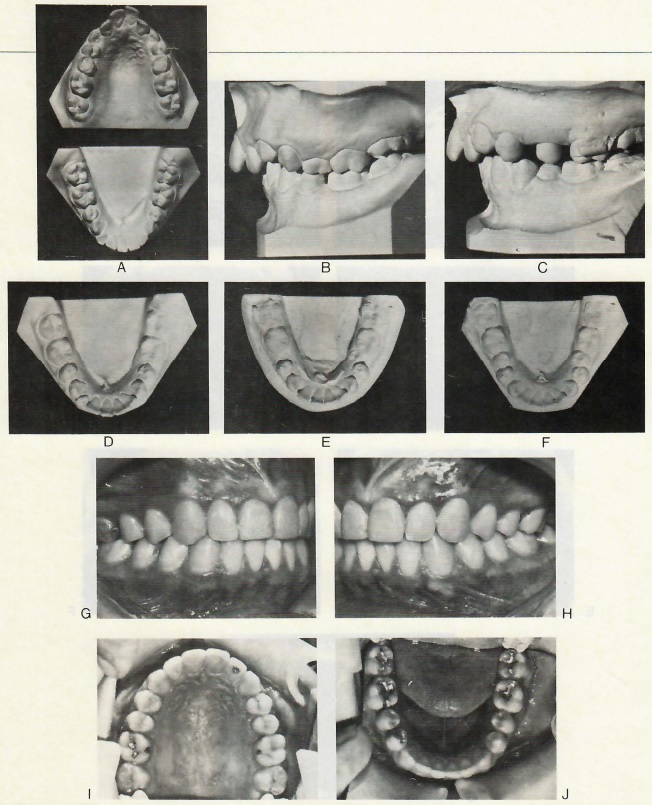

Fig. 2A Case 2. A-l. Before treatment. J-O. Space gained in maxillary and mandibular arches in one year.